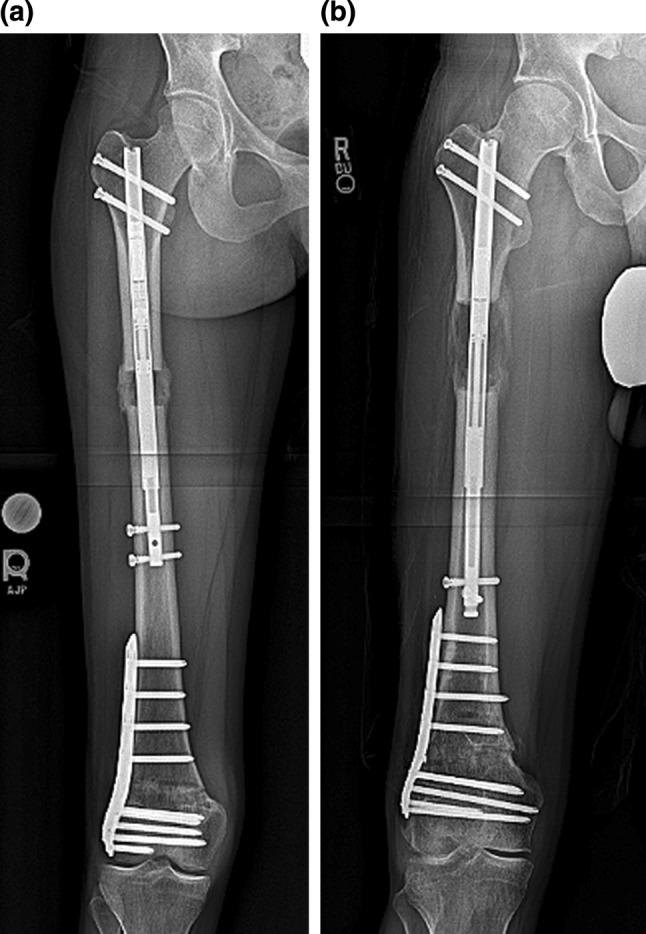

Salter Harris fractures of the distal femur can lead to growth disturbance with resulting leg length inequality and knee deformity. We have looked at a case series (3) of patients who presented with a distal femur flexion malunion and shortening treated with a distal femoral osteotomy and plating and a proximal femoral osteotomy with a magnetic internal lengthening nail. Does a two-level osteotomy and internal fixation approach provide a reliable result both radiographically and functionally? The average knee extension loss was 12°, LLD 47 mm, PDFA 65°, MAD 2 mm. The patients were treated with an acute, posterior, opening wedge osteotomy of the distal femur stabilized with a lateral plate and screws and grafted with cancellous chips and putty. A second osteotomy was made proximally in the femur percutaneously, and the internal lengthening nail was inserted. Lengthening was done at approximately 1 mm/day. The average extension gain was 12°; amount of lengthening at the proximal site was 40 mm, LLD was 3 mm. The average PDFA was 81°, and MAD 3 mm. There were no complications. Functional results were excellent. Bone healing index was 24 days/cm. The average distance from the distal osteotomy to the joint line was 57 mm. The technique of two-level femur osteotomy stabilized with a plate and lengthening nail yielded excellent results with acceptable correction of deformity, full knee extension, and improved function. There were no complications including implant failure, infection, need for blood transfusion, knee stiffness, nonunion, compartment syndrome, or malunion.

摘要